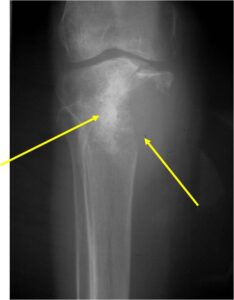

Radiology emulates pathology: Biphasic Tumor

- One region low grade chondrosarcoma

- Second more aggressive area with bone destruction, lysis of calcification, soft tissue mass

- Cortical permeation and a soft tissue mass in 70% of cases

Ill-defined, lytic intraosseous lesion

- Or extraosseous soft tissue mass

- Devoid of calcifications in continuity with lesions having the features of a cartilaginous tumor

Characteristically abrupt transition between chondroid tumor and dedifferentiated, lytic component

Bone may be expanded and adjacent cortex thickened